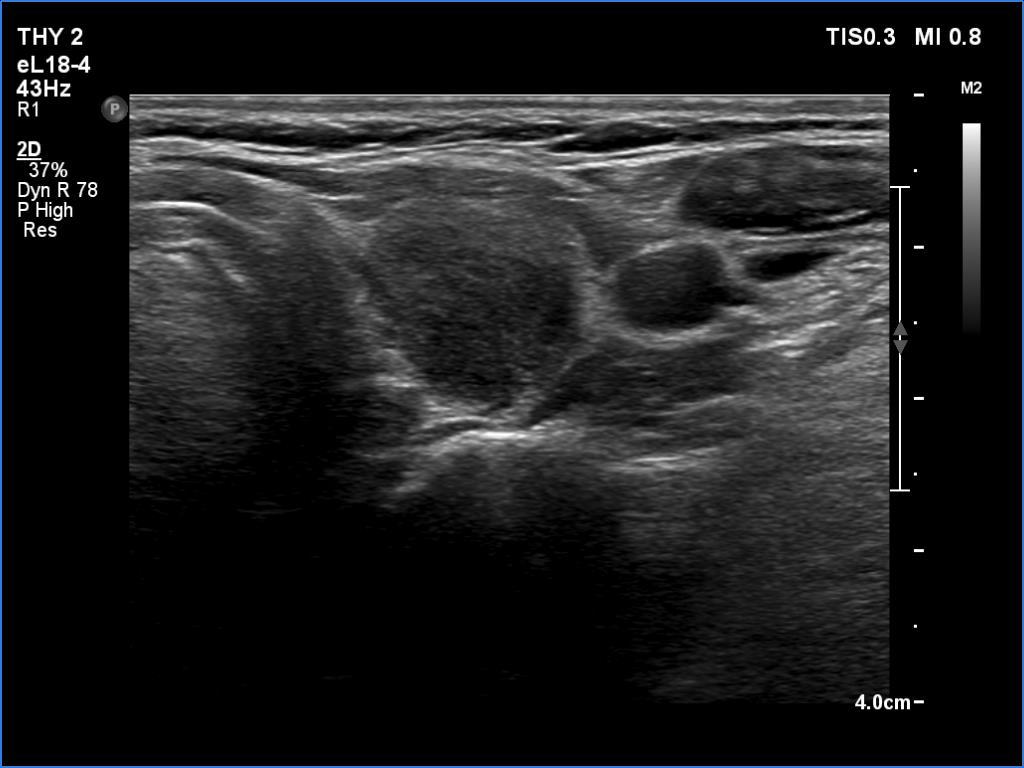

Lymphocytic thyroiditis - case 1441

Right lobe

Left lobe

Focal form of lymphocytic thyroiditis is presented. The thyroid has numerous discrete, hypoechoic lesions which correspond to more active foci of thyroiditis. The interpretation of the relatively large ventral hypoechoic area in the left lobe (right upper image can cause problem), however, longitudinal scan decides the issue: this field cannot be a pathological nodule.